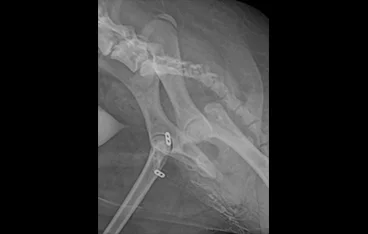

고관절 질환

THR, FHNO, Toggle pin

• THR

• THR 전

THR 후